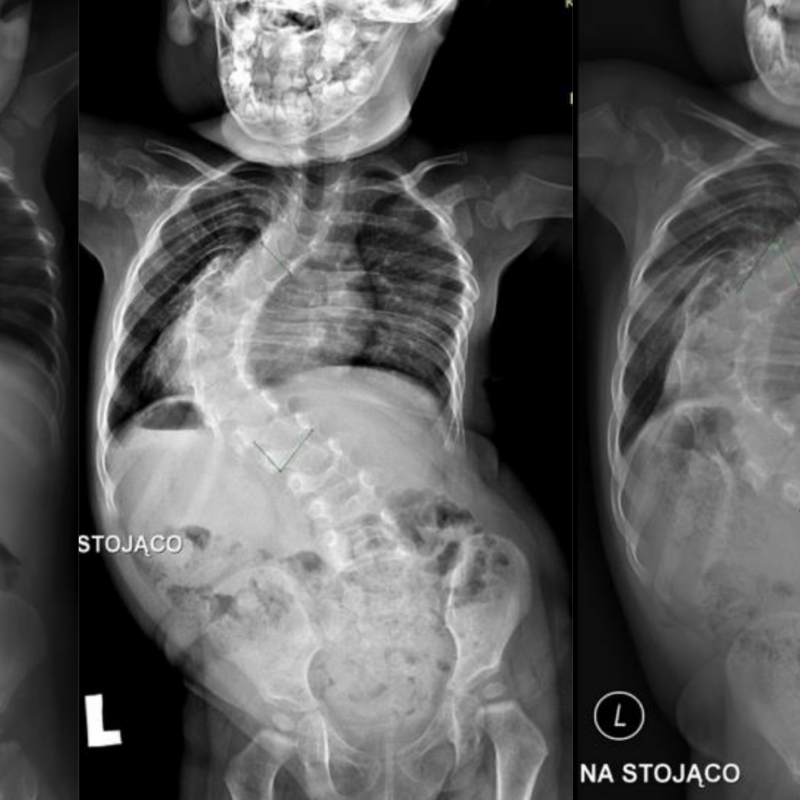

Scoliosis is a condition that causes the spine to curve sideways. Idiopathic scoliosis usually starts around the age of 10 and continues until the child is done growing. Many cases do not require surgery, but orthotic bracing is typically recommended in cases when a curve is between 25-45 degrees. The orthosis is used to prevent the curve from getting worse. Lawall has been treating kids with scoliosis for over 40 years. Harry J. Lawall Jr. worked closely with the doctors at Nemours to use the Wilmington Brace, which is still being used today. But Lawall pediatric specialists are well versed in all options for scoliosis bracing such as the Boston Brace and Charleston Bending Brace. The course of treatment always depends on the patients presentation and physicians decision regarding the course of treatment.